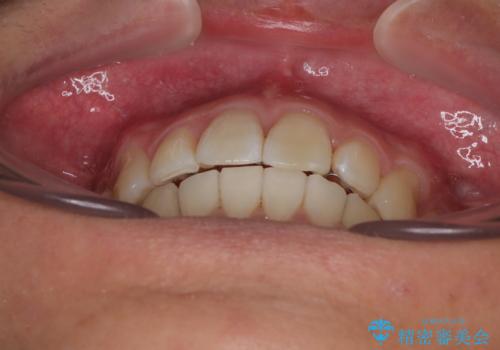

前歯のデコボコをインビザラインで綺麗に改善

- 上下前歯のデコボコとクロスバイトを気にして来院された患者様です。

インビザラインを用い、IPR(歯と歯の間を削る)と歯列全体を拡大させることで、歯並びを整えていくこととしました。

毎日22時間の装着時間を徹底してくださったのですが、左右ともに臼歯が咬合しなくなるという、インビザライン独特の症状が強く長く続いてしまい、終了するまでに長期間を要してしまいました。